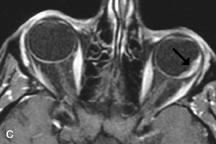

Lymphomas have MRI characteristics similar to those of inflammatory lesions in that they are hypointense to fat and isointense to muscle on T1-weighted images (Fig. 22). They may appear hyperintense to fat on T2-weighted images, perhaps owing to less fibrosis than that seen in orbital inflammatory pseudotumor, although this is not a consistent finding.31,50,66 Lymphoid tumors typically enhance moderately after contrast injection. Unfortunately, studies have shown that tumor density and homogeneity are similar between inflammatory and malignant orbital infiltrates, and MRI cannot differentiate these lesions.72,73

Fig. 22. A and B. T1- and (C) T2-weighted MR scans demonstrate a poorly defined multicompartmental mass enveloping the lateral rectus, superior rectus, and levator palpebrac superioris muscles. The lesion is isointense to brain on T1- and T2-weighted scans, as is typical for highly cellular neoplasms. D. Postcontrast fat-suppressed T1-weighted scan demonstrates intense enhancement of the infiltrating intraconal and extraconal tumor.